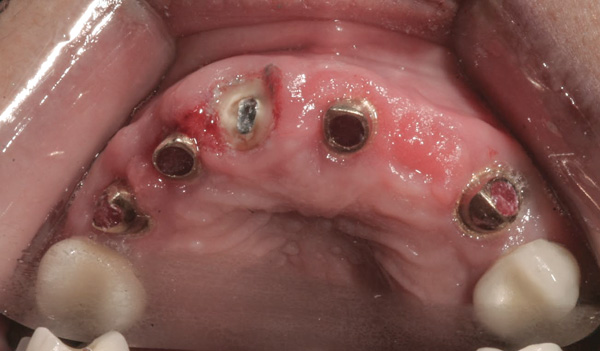

Background: In this case, the patient had a failing mandibular and maxillary dentition due to caries secondary to radiation-induced xerostomia. The patient had had a radical neck dissection to remove a squamous cell carcinoma of the throat 9 years prior to his prosthodontic consultation with the authors. The patient reported a history of radiation therapy following surgery, but did not have a shielding stent. A staged approach was used so as to avoid removable prosthetics on his severely dry soft tissues. He chose to treat his mandibular issues first. Figure 9 shows healing abutments next to the temporarily retained natural teeth, and Figure 10 shows the first-stage custom abutments inserted with relatively good gingival contour and no recession. Recession was clearly seen around all first-stage abutments following adjacent extractions and second-stage implant placement (Figure 11).

Results: The decision was made to remove these abutments and make a fixture-level impression of all the implants so that both new and first-stage abutments could be milled together for parallelism and proper gingival margin location. Because this requires the removal of the first-stage abutments that were retaining the provisional prosthesis, temporary abutments were placed prior to removal of all custom abutments in order to assure proper seating and vertical dimension of the provisional. These temporary abutments then retained the provisional while all custom abutments were fabricated and/or milled in the laboratory. Figure 12 shows the placement of the remilled (first-stage implants) and new (second-stage implants) custom abutments.

Figure 12 Remilled and new custom abutments.

Figure 12